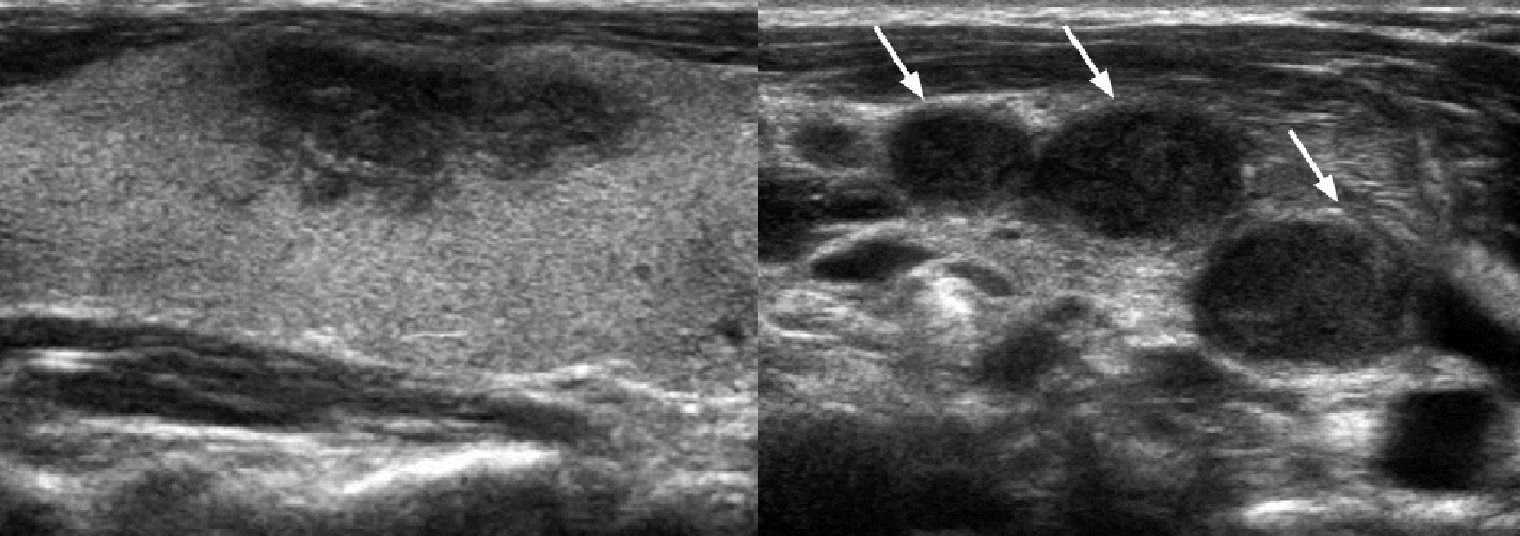

При тиреоидите де Кервена щитовидная железа диффузно или локально увеличена; в области наибольшей болезненности определяются крупные гипоэхогенные участки неправильной формы с размытыми границами (наиболее выражено снижение эхогенности в центре «пятна»), кровоток в аномальной зоне почти отсутствует; часто увеличены региональные лимфоузлы. Наличие гиперэхогенных структур не характерно. В процессе рубцевания поврежденная ткань может замещаться фиброзной, но в большинстве случаев восстанавливается нормальная структура железы. Подробнее смотри Аутоиммунная щитовидная железа на УЗИ (лекция на Диагностере).

Рисунок. На УЗИ в правой доле щитовидной железы в области максимальной болезненности определяется крупный гипоэхогенный участок неправильной формы, без четких границ, кровоток в аномальной зоне отсутствует. Шейные лимфоузлы увеличены, гипоэхогенные, округлые. Заключение: Подострый тиреоидит де Кервена. При такой ультразвуковой картине необходима дифференциальная диагностика с карциномой щитовидной железы.